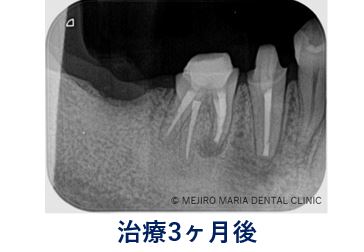

経過3ヶ月後、歯肉の腫れや痛みは消失し、同時に術前より見られていた右下4番、5番の歯周ポケットも改善したのを確認。

また、手術直後のレントゲン写真から比較すると、術後3ヶ月のレントゲン写真では順調に骨が作られていることが確認できる。

右下5番6番の透過像(黒い影)は2019年11月の経過観察時に消失し、その後安定していることがレントゲン写真より確認できる。